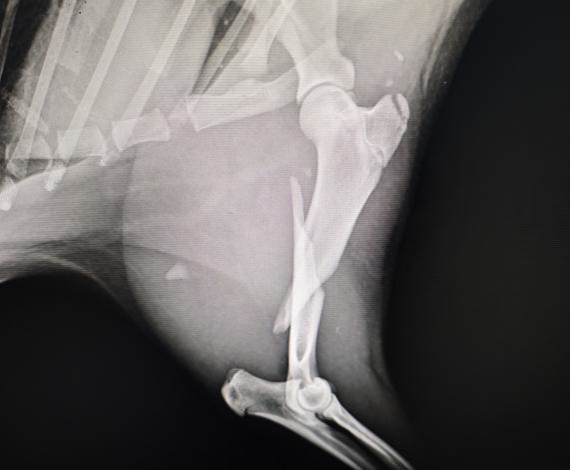

拍摄水豚左前肢X光

手术前左前肢侧位X光